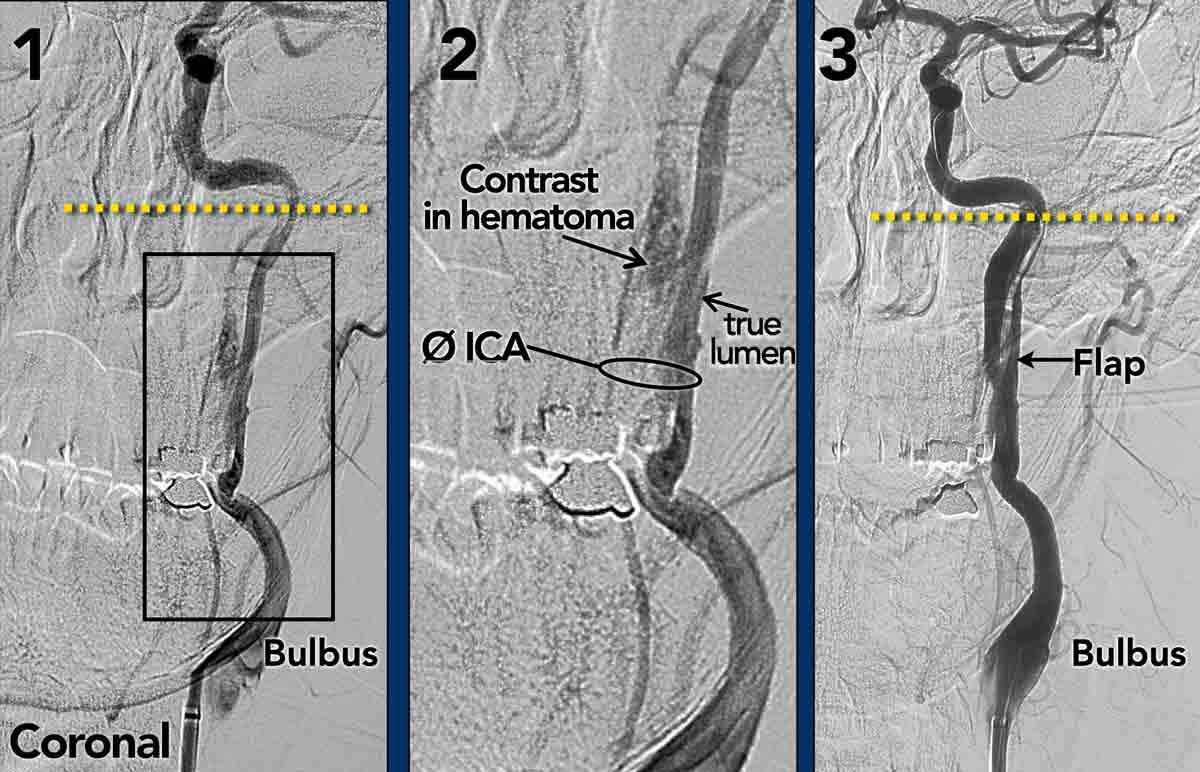

Bóc tách trên DSA

Tất cả các dấu hiệu đã thảo luận trên CTA đều tương tự và thậm chí rõ ràng hơn trên DSA.

- Catheter được đặt tại mức phình cảnh (bulbus), có hình ảnh bình thường.

Vài centimet phía trên phình cảnh, lòng mạch ICA bị lệch tâm và bị chèn ép bởi khối máu tụ thành mạch (thấy rõ hơn trên hình chi tiết số 2).

Tại mức nền sọ (đường chấm vàng), mạch máu trở về bình thường. - Hình chi tiết cho thấy thuốc cản quang đã thâm nhập vào trong khối máu tụ.

Lưu ý tổng đường kính ICA bị giãn rộng. Mũi tên chỉ lòng mạch thật sự. - Sau điều trị nội mạch, sự thông thoáng của ICA đã được phục hồi.

Khối máu tụ thành mạch phần lớn đã được tiêu huyết khối thông qua điều trị tĩnh mạch bằng chất hoạt hóa plasminogen mô tái tổ hợp (rt-PA, alteplase) trước khi can thiệp nội mạch. Vạt nội mạc (intima flap) vẫn còn nhìn thấy. Một lần nữa, bạn có thể thấy vạt nội mạc dừng lại tại mức nền sọ.